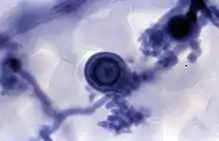

Применяется в микроскопии для прижизненного окрашивания по Гольдману, также используется для гистологических целей[3].